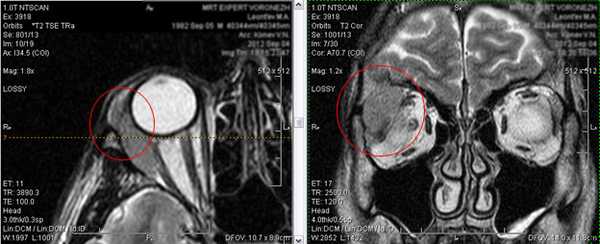

5. Объемные образования орбит.

В орбитах с обеих сторон, более выражено справа, определяются множественные дополнительные образования. Образования интимно прилежат к стенкам глазниц, мышцам глаза. Часть из них - расположены изолированно в орбитальной клетчатке без достоверных признаков прилежания к структурам глазниц.